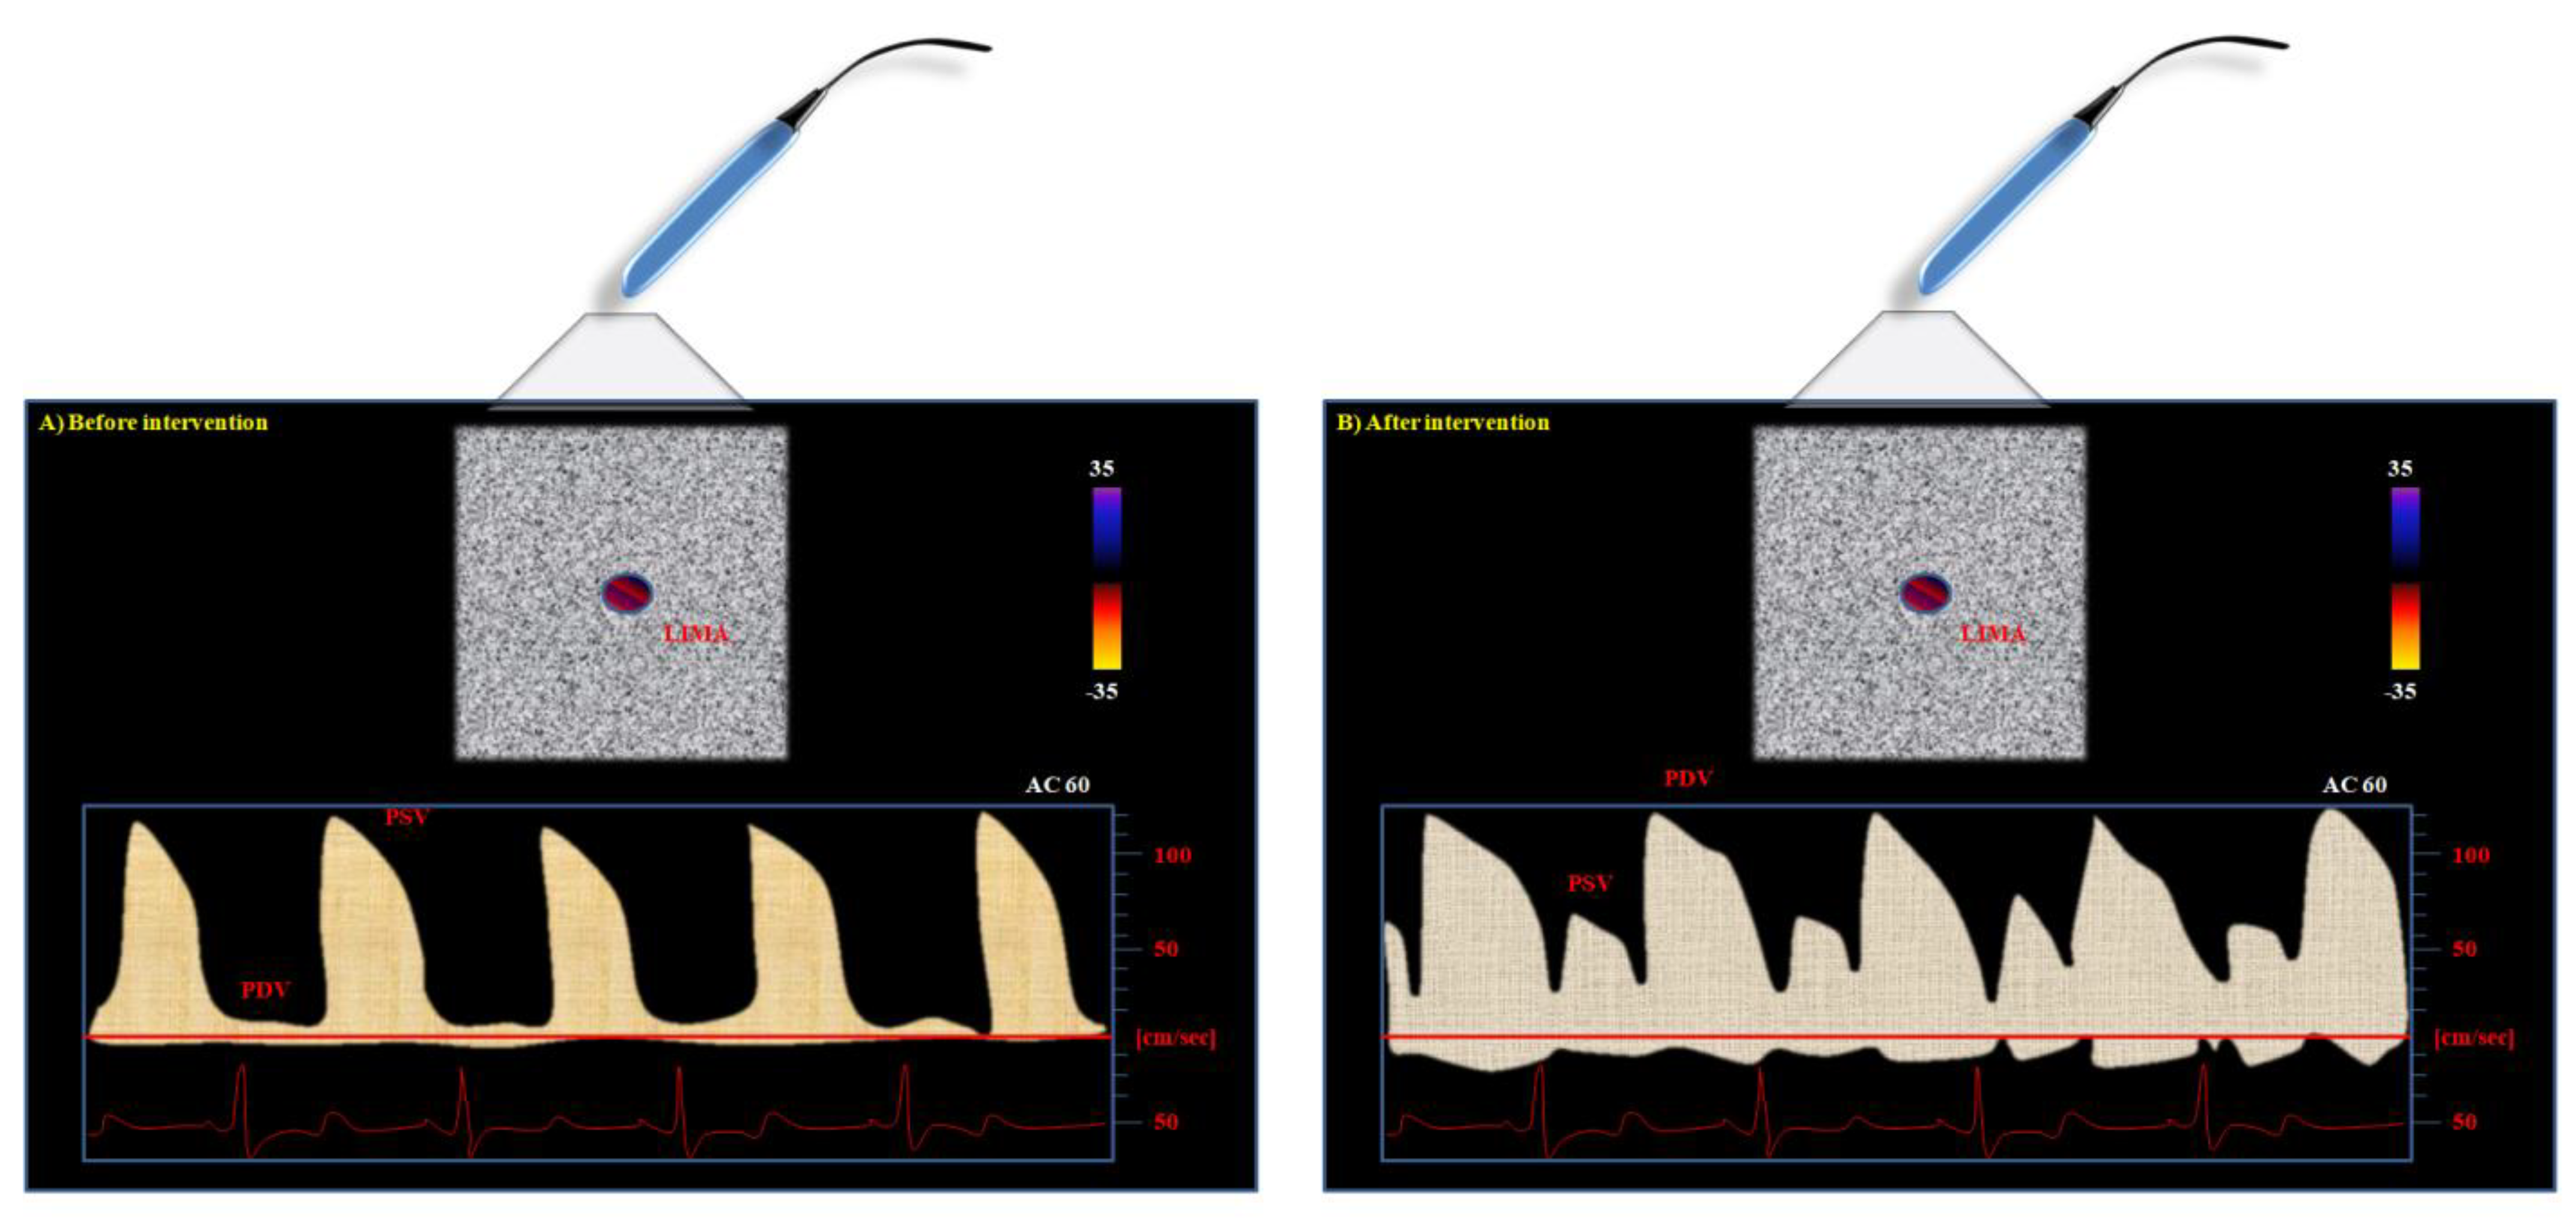

The normal, not-anastomized LIMA typically shows a CW pattern characterized by higher systolic and minimal diastolic waves (Figure 2).

The reason is related to the physiology of the vascular cycle: peripheral vascular beds are normally perfused during the systole, thus accounting for the higher peak of systolic Doppler profile as compared to diastolic one in vessels still not-anastomized to the coronary arteries. After the by-pass intervention, the situation of perfusion changes. The coronary artery is usually perfused during diastole. Therefore, the LIMA can show a new, double situation after its connection to the LAD (Figure 2): it can maintain the systolic peak, but a more pronounced diastolic peak can be observed if the graft perfusion is not compromised [47,48,49].

Figure 2. Left internal mammary artery (LIMA) continuous-wave color Doppler flow aspect from the supraclavicular window: (A) before aorto-coronary bypass graft (CABG) intervention, and (B) after CABG intervention. The differences in Doppler profile (i.e., peak systolic (PSV) and diastolic (PDV) velocities) can be observed.